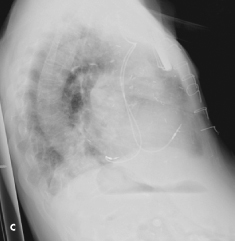

An ECG revealed a ventricular paced rhythm with right bundle-branch block (BBB) morphology and ex- treme axis deviation (A). The anteroposterior (AP) chest radiograph showed normal placement of the electrodes (B); however, the lateral film revealed a posterior deflec- tion with the ventricular electrode entering the coronary sinus and resting in a contributory branch (C).

Right BBB morphology during pacing requires further studies to determine the cause. As demonstrated in this case, the lateral chest radiograph is an essential part of the routine postoperative follow-up of patients with pacemakers. However, both AP and lateral films may be normal in patients with inadvertent coronary sinus lead placement.1Echocardiography, which may be impractical, and intracardiac ECG, which is ideally performed in the electrophysiology laboratory immediately after implantation, also can be used to confirm correct electrode placement.